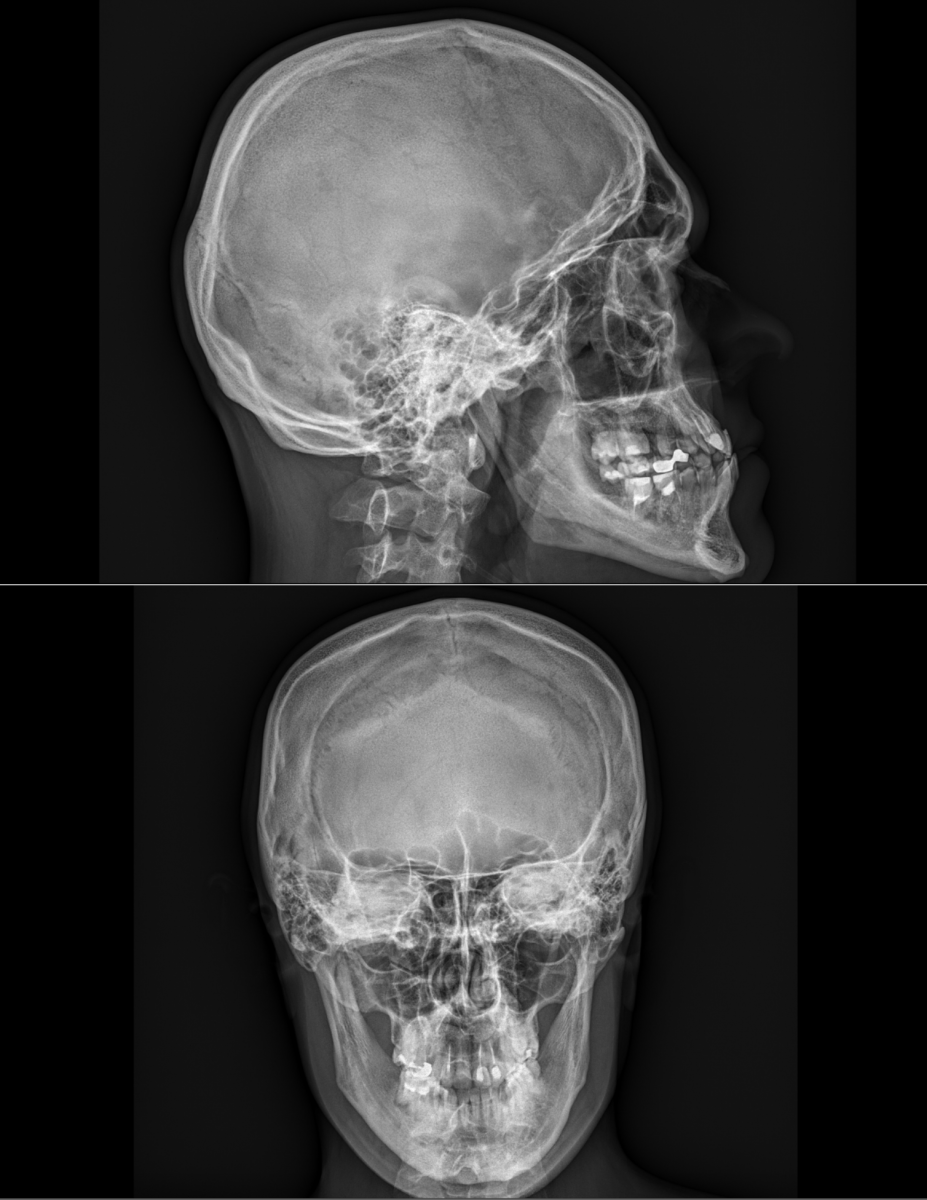

Ukázky RTG snímků